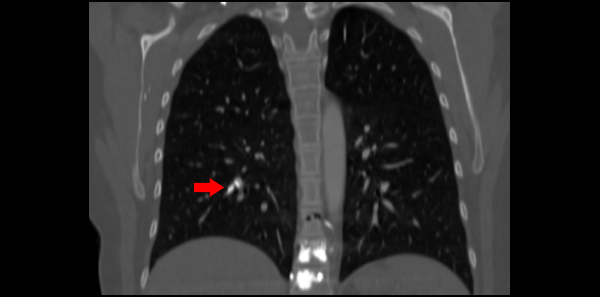

Laboratory testing was significant for a white blood cell count of 14.3 K/uL, hemoglobin of 17.8 g/dL, and a platelet count of 548 k/uL, all of which were consistent with hemoconcentration. ECG showed sinus tachycardia with a rate of 111 bpm. There were no ischemic changes or evidence of right heart strain. Troponin T and brain natriuretic peptide were within normal limits. CT angiography was obtained due to concern for pulmonary embolism and showed numerous hyperdense foci within the pulmonary arteries (see arrows in Figure 1) consistent with embolized polymethyl methacrylate (PMMA). While in the emergency department, the patient’s pain and nausea were treated symptomatically. She was given lactated ringers due to concern for dehydration. After a period of observation in the department, the patient requested discharge.

The patient stated that one year prior she was involved in a fall and as a result suffered T10–T11 compression fractures resulting in a kyphoplasty. Imaging after the procedure showed evidence of cement noted in the subsegmental pulmonary arteries of the right lower and left upper lobes. She had a resulting follow-up transthoracic echocardiogram that showed elements of pulmonary hypertension, which was confirmed with right heart catheterization. As a result, the patient had been dealing with chronic right-sided chest pain since the event and required pain management intervention. In addition, her hematologist recommended anticoagulation with warfarin for six months, which she had completed.